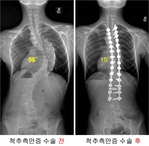

‘S’자 척추 측만증 1,000례 이상수술 기록 달성